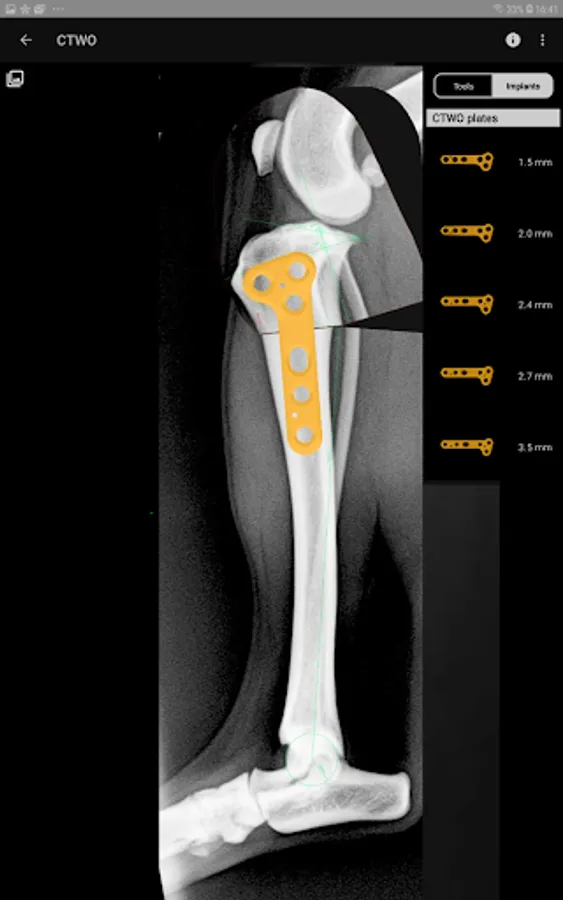

This is a useful tool for traumatology and orthopaedic surgical planning veterinary, including advanced techniques for treat canine anterior cruciate ligament (ACL) injuries (TPLO and CTWO).

4. Catalogue of BETA Implants locking plates, in 2.0, 2.4, 2.7 and 3.5 sizes:

l) CTWO plates